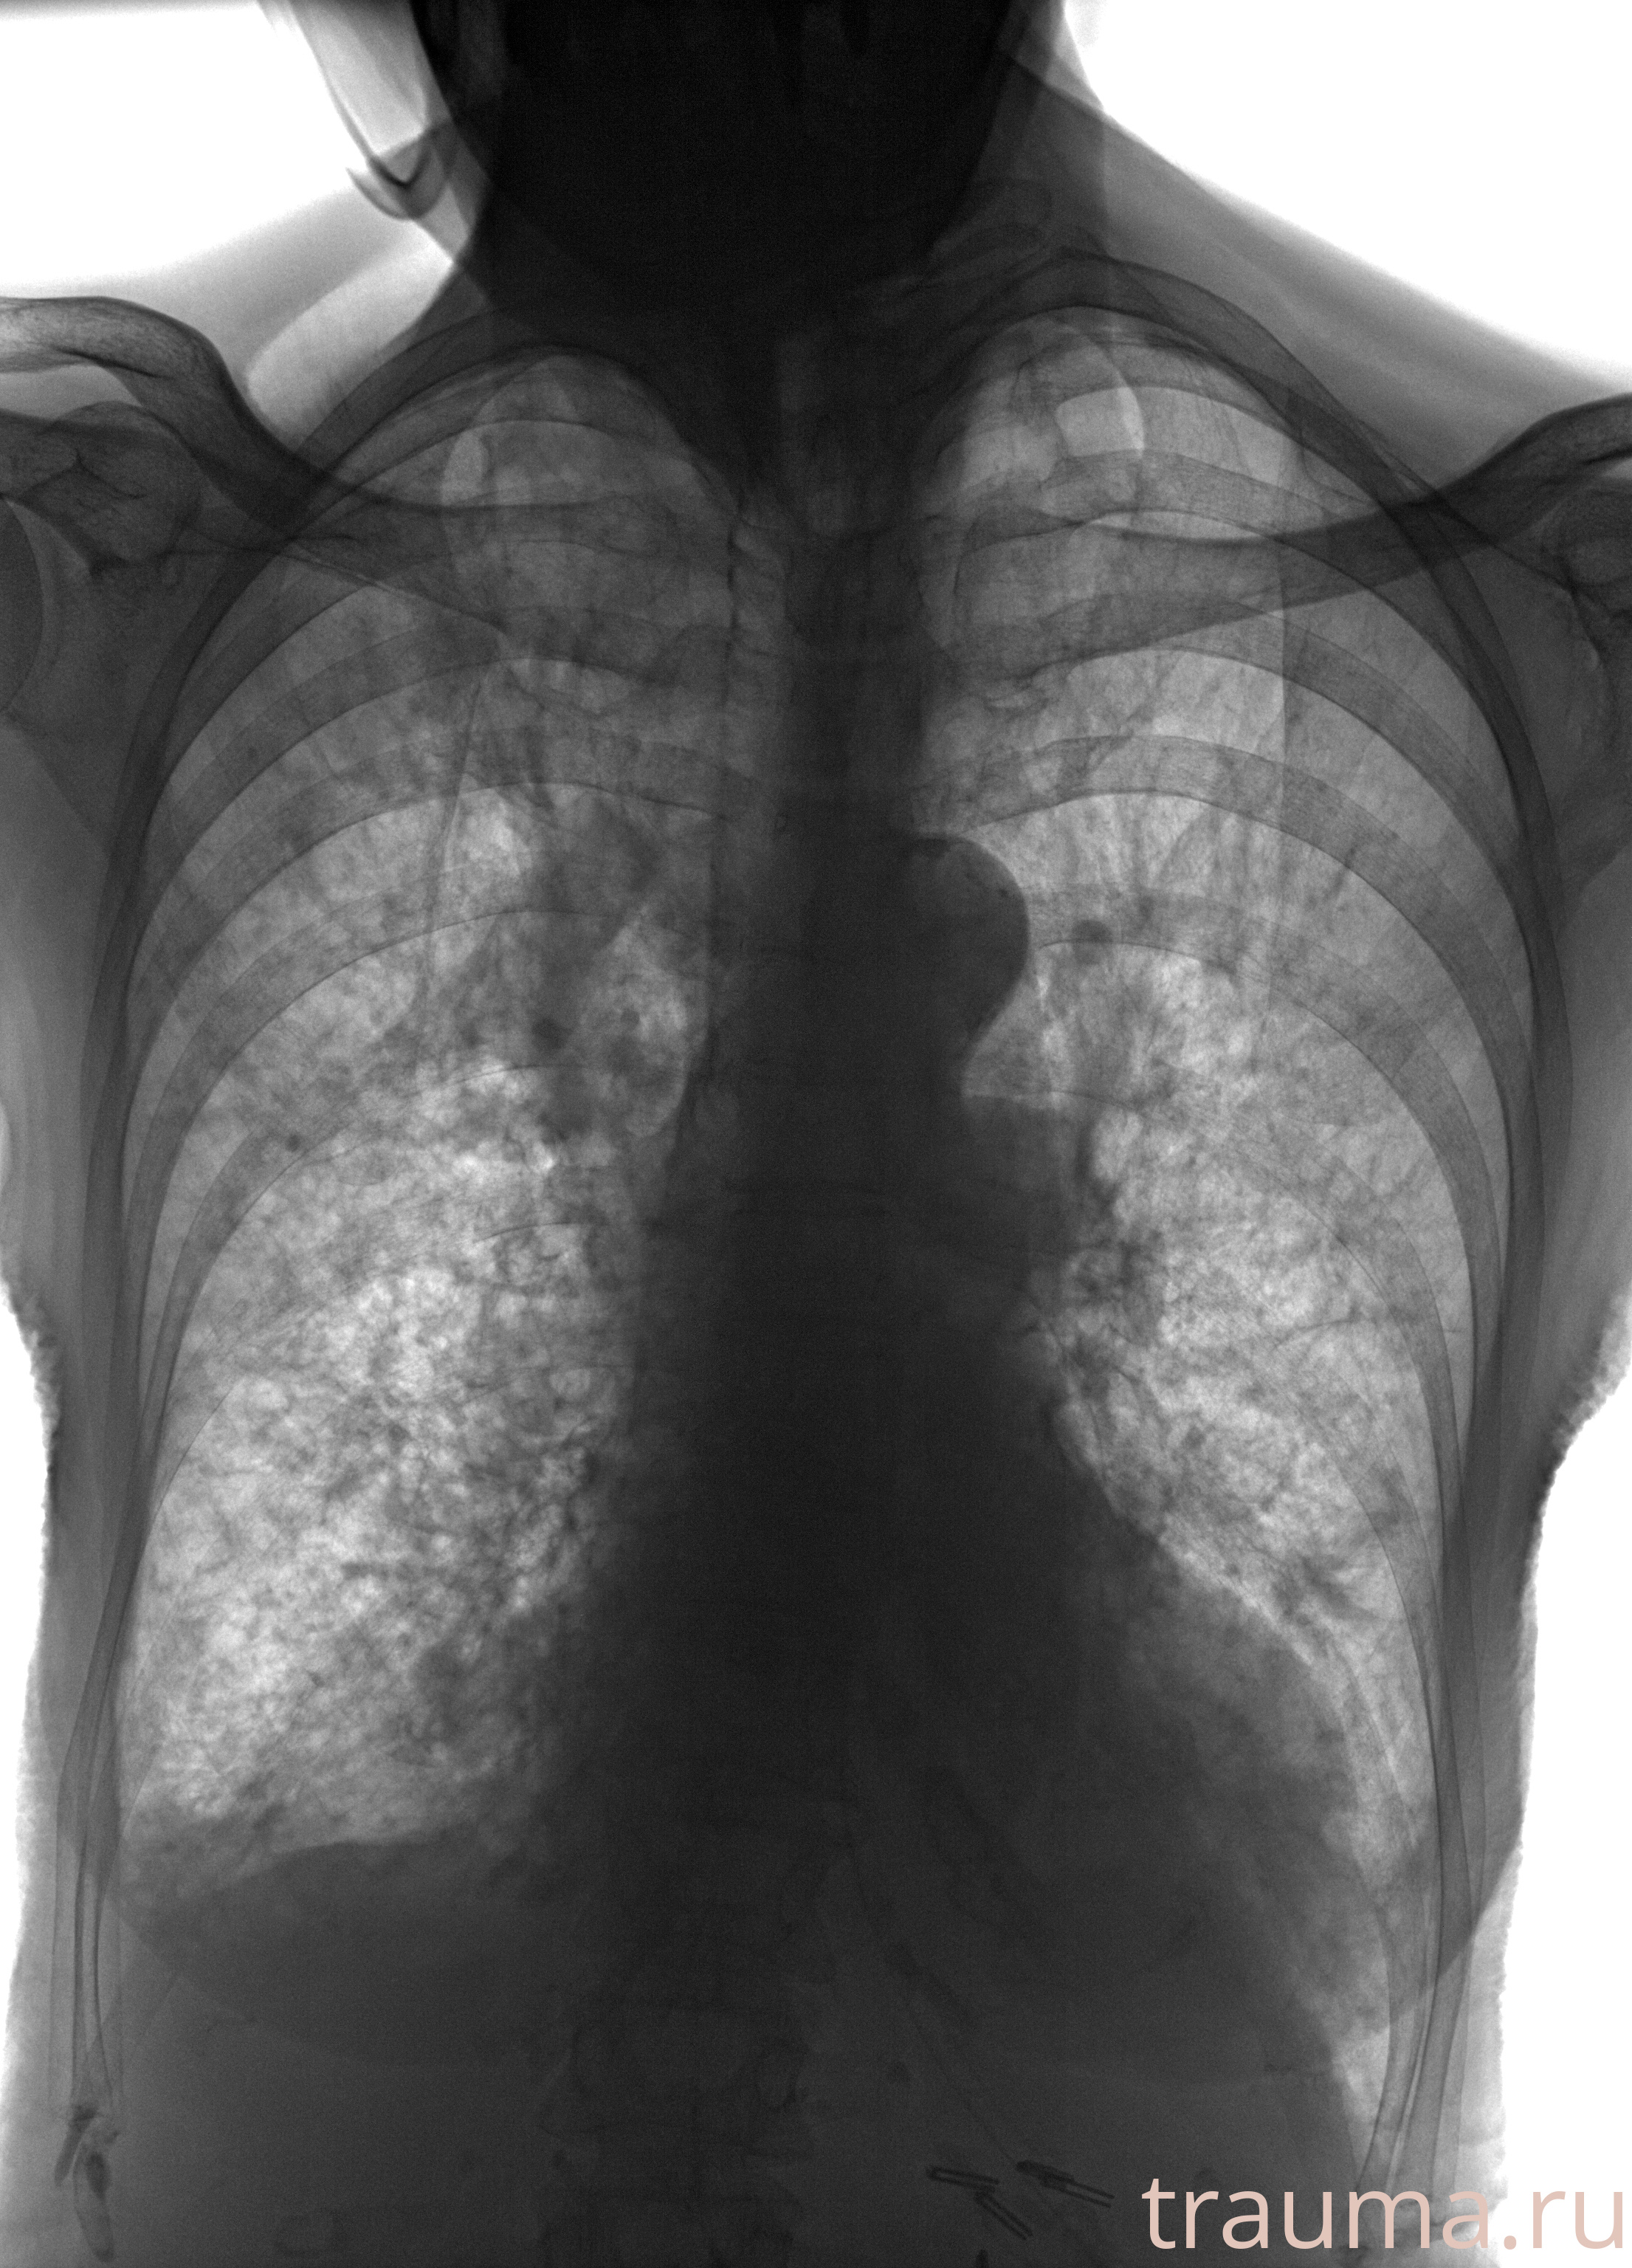

Рентген на дому: по вашему адресу приезжает врач-рентгенолог, травматолог-ортопед с мобильным рентгеновским аппаратом, проводит диагностику травмы или заболевания, делает необходимые рентгенограммы, дает рекомендации по дальнейшему лечению. Получить качественные снимки в домашних условиях возможно благодаря уникальной методике, разработанной МосРентген Центром для института  Склифосовского

при переломе шейки бедра и пневмонии от компании МосРентген Центр - партнера Института имени Склифосовского